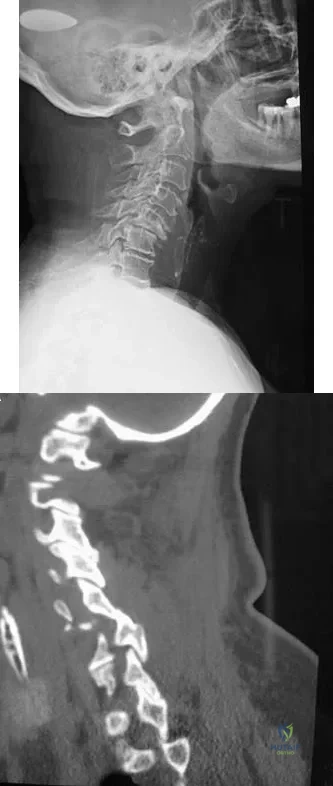

A 65-year-old woman has significant neck pain after falling and striking her head. A radiograph and sagittal CT scan are shown in Figures 23a and 23b. What is the most likely diagnosis?

Explanation:

The radiograph shows a displacement of C5 on C6 of approximately 25%. The CT scan shows a perched facet at C5-6. There is no evidence of a facet fracture. A bilateral facet dislocation would show a displacement of more than 50%. Rothman RH, Simeone FA (eds): The Spine, ed 4. Philadelphia PA, WB Saunders, 1999, pp 927-937.